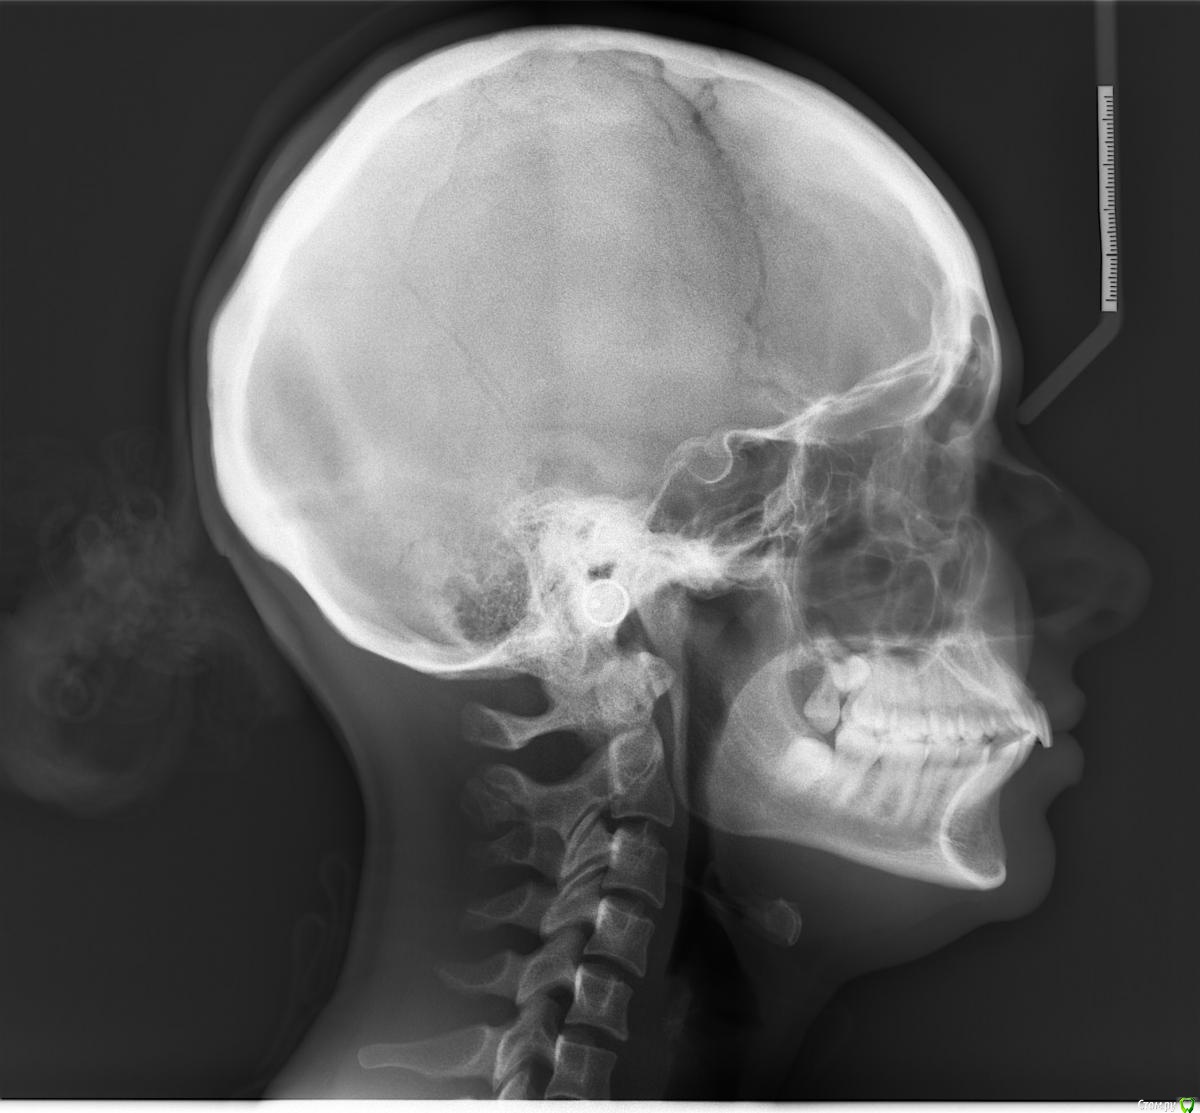

Коррекция дистального и глубокого прикуса

Я давно мечтала об идеальной улыбке и наконец-то решилась сходить к ортодонту.

У меня зубы более менее ровные, вот только с прикусом что-то не так.

После консультации ортодонта я была очень расстроена, так как мне было прописано удаление 8-ми зубов. 4-х мудрости (с этим я в принципе согласна и готова) и 4-х примоляров (они у меня совершенно здоровые) и брекеты на 1,5-2 года.

Для того чтобы подтвердить диагноз я решилась пойти еще к 3-мь специалистам и они мне озвучили тот же вердикт.

Только последний врач сказал что 4-ки удалять мне не нужно, так как моя нижняя челюсть и так слабо развита и в случае удаления примоляров у меня испортится профиль и будет прикус как у старушки. Ортодонт сказал, что нижнюю челюсть наоборот требуется выдвинуть вперед  с помощью брекетов и резинок. Только мне необходимо подрезать уздечку языка (якобы из за того что она плотнее чем нужно, она тянет нижнюю челюсть назад. Я слабо себе это представляю, но мне так озвучили).

Я не знаю кому верить, так как боюсь себе навредить и испортить лицо :( .

Возможно мне вообще требуется хирургическое вмешательство и любые брекеты только испортят ситуацию.

Мои снимки к письму прилагаются.